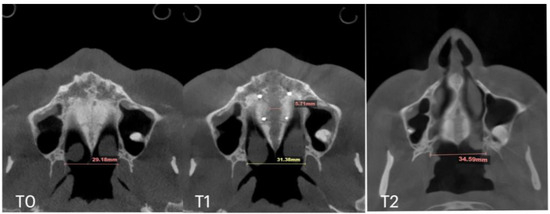

| Case B | 30.61 | 34.41 | 34.97 | 59.73 | 63.47 | 60.56 | 31.79 | 34.6 | 35.35 | 29.18 | 31.38 | 34.59 | 5.7 |

| Case C | 28.40 | 38.32 | 36.72 | 53.63 | 62.43 | 59.80 | 31.29 | 38.45 | 38.51 | 29.15 | 35.8 | 35.36 | 8.47 |

| Case D | 26.25 | 33.27 | 31.54 | 55.9 | 61.84 | 60.37 | 33.98 | 35.94 | 38.09 | 29.77 | 29.24 | 29.02 | 6.2 |